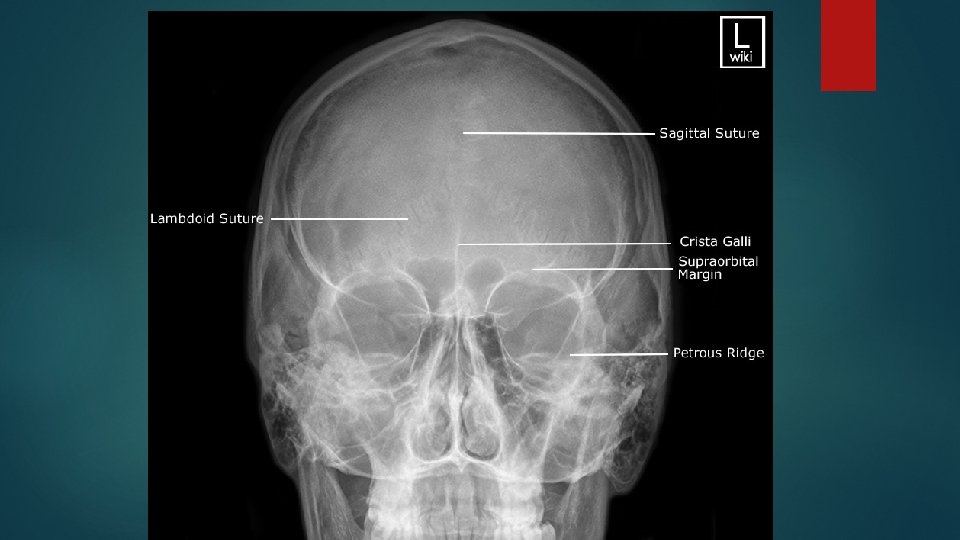

Occipito frontal view Positioning of patient : Patient is seated facing the erect bucky, so that the median sagittal plane is with the midline of the bucky and perpendicular to it. Neck is flexed to bring orbito meatal line perpendicular to the bucky, this can be achieved by ensuring the nose and forehead are in contact with the bucky.

Central ray : Ray is directed perpendicular to the bucky along the median sagittal plane and at the level of nasion. Image should include the vertex superiorly and base of occipital bone inferiorly

Caudal angulation : OF 0 deg : the petrous ridges completely superimposed with orbit OF 10 deg : the petrous ridges appears in the middle third of the orbit OF 15 deg : the petrous ridges appears in the lower third of orbit OF 20 deg : the petrous ridges appears just below the inferior orbital margin.